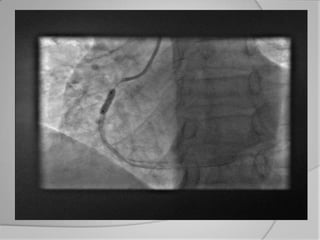

 Infarctus aigus avec choc

cardiogènique:

Cette catégorie de patients a la plus

haute mortalité et nécessite un

diagnostic et traitement invasif précoce

et aussi fréquemment un soutien

cardiovasculaire mécanique avec

pompe à ballon de contre pulsion

aortique

   les patients avec le plus haut risque (infarctus avec surélévation ST,

choc cardiogène) sont acheminés dans le cas idéal directement en

salle de cathétérisme.